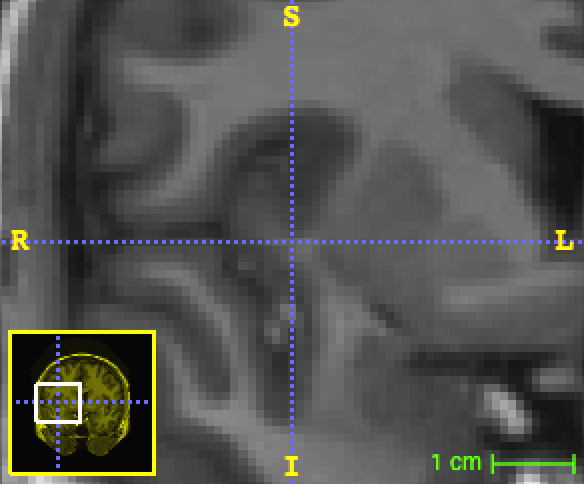

Refer to caption

Figure 5: Example of three orthogonal patches centred on the voxel of interest. Screenshots captured with ITK-SNAP.

We set out to study the performance of SegNet on this dataset despite the fact that deep learning techniques generally require much larger training datasets. All computations had to be run in-memory using a single NVIDIA Tesla K40 GPU with 12GB memory. Therefore we faced a trade-off between the number of datapoints and the number of dimensions of the dataset. On the basis of initial tests, we decided to extract randomly and uniformly across the brain a sample of approximately 202020k voxels from each one of the 151515 atlases, for a total of 300300300k voxels for training purposes, which amounts to only approximatively 1.5%percent1.51.5\% of all the available voxels in the dataset. For each voxel, we extracted a 737773777377-dimensional input vector consisting of a 3D patch of 133superscript13313^{3} voxel intensities (a=13𝑎13a=13), three 2D orthogonal patches of 292superscript29229^{2} voxel intensities (b=29𝑏29b=29), three 2D downscaled patches of size 292superscript29229^{2} containing averaged voxel intensities (the original patch width is 878787 and the scale is 333, i.e. c=29𝑐29c=29, s=3𝑠3s=3) and 134134134 distances to centroids. Figure 5 shows a sample of 2D patches. A validation dataset consisting of 404040k data points was also extracted from the the 15 atlases.